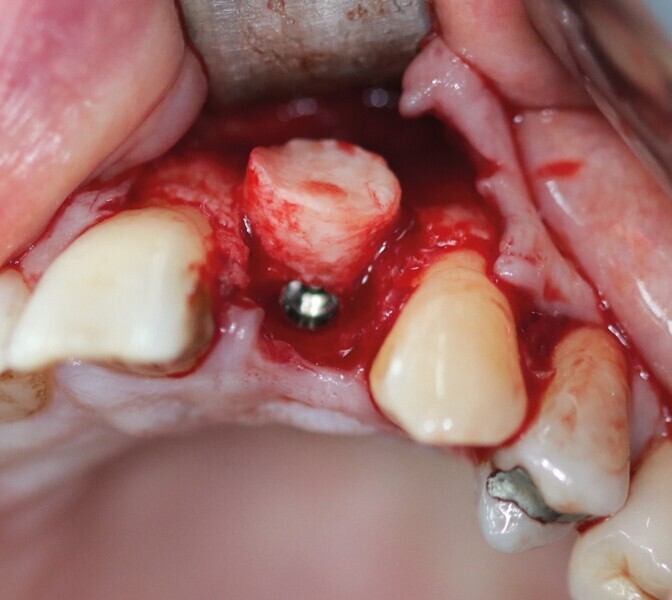

Dans les cas cliniques présentés dans cet article, la carotte osseuse fournit une table osseuse de forme circulaire, et son immobilisation est par impactage et non par vissage. Ce sont ces deux particularités qui nous permettront de placer l’implant dans le même temps opératoire. En effet, la carotte osseuse est désépaissie en la coupant en deux en épaisseur. Une partie est transformée en copeaux d’os et mélangée à l’os de forage, récupéré dans les rainures des forets BLT Straumann (Fig. 15). Une fois l’implant parfaitement ancré (Fig. 16), cet os particulaire est placé contre la surface implantaire (Fig. 17). La rondelle corticale restante est impactée et sert ainsi de mur vestibulaire (Fig. 18). Cet ensemble se retrouve parfaitement dans les contours osseux. L’implant ayant une stabilité primaire suffisante, une dent provisoire en composite sur pilier PMMA est transvissée.

Pour connaître la profondeur de trépanation, il suffit d’enfoncer la sonde parodontale et de mesurer l’épaisseur de gencive sur l’os. En y ajoutant 4 mm, la profondeur finale est obtenue pour avoir suffisamment d’os. Une fois la carotte ostéogingivale prélevée (Figs. 23 et 24), il ne faut pas séparer l’os de la gencive, mais réduire l’épaisseur gingivale en supprimant la partie kératinisée (Fig. 25). Un implant cylindroconique (Straumann BLT 3,3 SLActive Roxolid) est parfaitement ancré (Fig. 26). La carotte d’os et sa gencive toujours adhérente, sont alors impactées transversalement à l’implant (Fig. 27). La partie osseuse spongieuse est au contact de l’implant, pendant que le conjonctif qui y est attaché, est utilisé comme un greffon conjonctif enfoui sous le lambeau vestibulaire.